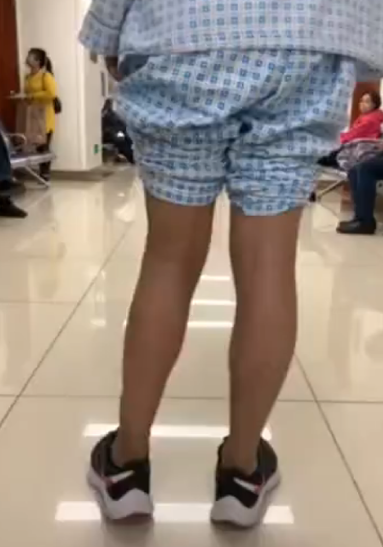

膝关节外翻,后面观